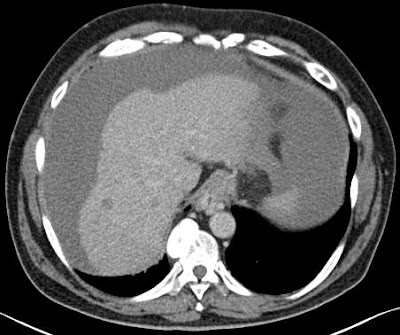

a műtét utáni UH-vizsgálat a v. umbilicalis tágulatát mutatja szabályos áramlássalnatív méréscoronalis recon (az elváltozás körbeveszi a ligamentumot)mellkas Ct vizsgálat (hasi szelet) axialis rekon – a lig falciforme hepatis mellett egynemű, sűrű folyadék...